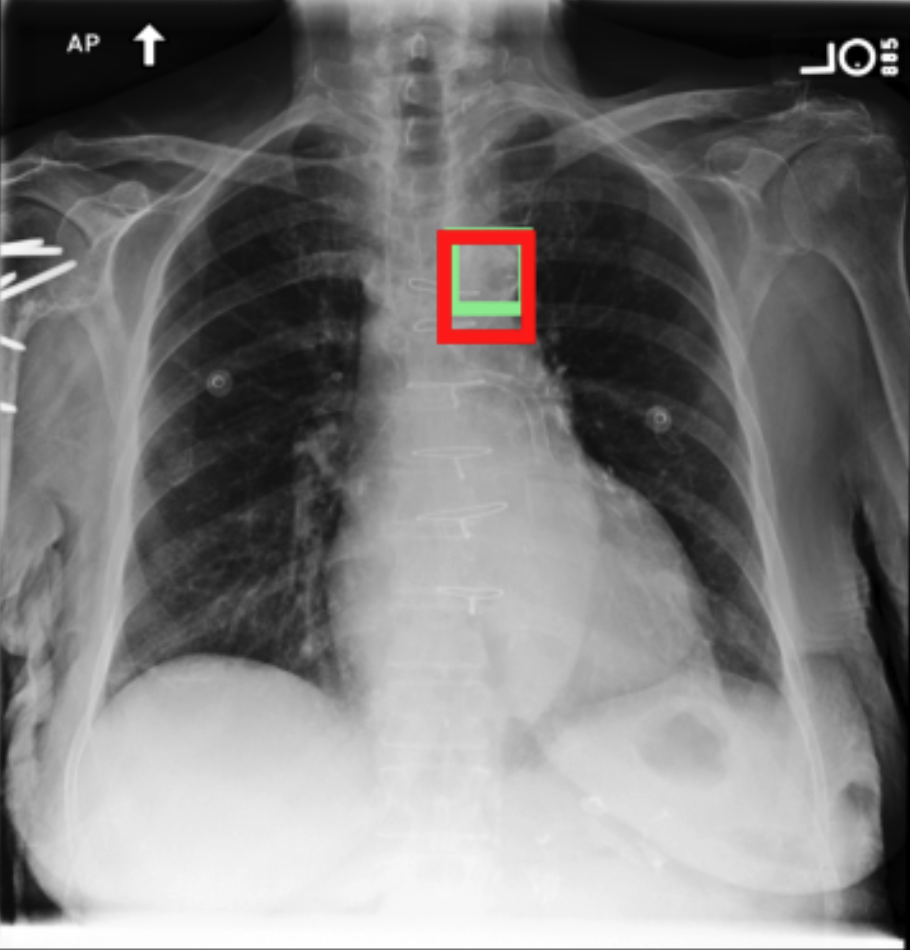

4.3.3 Visual grounding

In this section, we evaluate RadVLM’s visual grounding capabilities, which could help clinicians localize specific regions or pathologies on a CXR. This is particularly useful once a pathology has already been identified – either by a radiologist’s input or through our previously described AI tasks – since it allows one to pinpoint exactly where the abnormality appears on the image.

We report performance metrics for the three main grounding tasks RadVLM was trained on: anatomical grounding using the Chest Imagenome test set, abnormality grounding using the VinDr-CXR test set, and phrase grounding using the MS-CXR test set (Table 1). For each task, we use mean Average Precision (mAP) as our primary evaluation metric.

Our results show that RadVLM performs well at localizing anatomical regions (e.g., “right lung”, “aortic arch”, illustrated in Figure 5a), achieving a mAP of 85.8 %, by far surpassing the other CXR grounding models (Table 4). This advantage is partly explained by including the Chest Imagenome dataset (and thus the anatomical grounding task) in the training set, which CheXagent and MAIRA-2 did not leverage. However, it remains a key feature for any grounding model to possess a fine-grained understanding of CXR anatomy.

For the abnormality grounding task, RadVLM is less consistent (Figure 5b), likely due to higher sparsity of abnormality locations and labels, yet it still achieves best performance (Table 4). For the phrase grounding task, while MAIRA-2 and CheXagent demonstrate great performance, RadVLM surpasses them with a mAP of 81.8% (Table 4), presumably benefiting from the newly released PadChest-GR dataset (Castro et al.,, 2024) used for training.

Overall, these results show that our instruction tuning strategy for visual grounding (covering three essential tasks), combined to a modern VLM backbone, offers a promising avenue to help clinicians localize anatomical and pathological features during a CXR exam. Furthermore, providing fine-grained details within an LLM-generated output may also enhance the ability to answer grounded questions in a multi-turn setting, as we explore next.

a. Anatomical grounding

silhouette

junction

structures

lung

abdomen

mediastinum

arch

b. Abnormality grounding

thickening

fibrosis

enlargement

lung disease